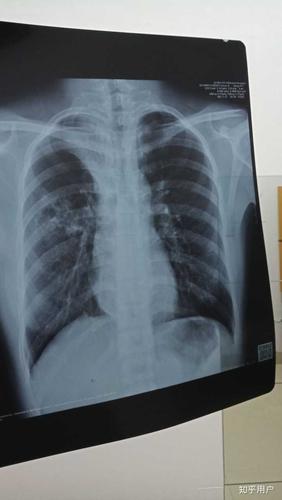

肺结核咳出坏死物图片

肺结核

空洞型肺结核

肺结核ct

肺结核图片

肺结核x光片